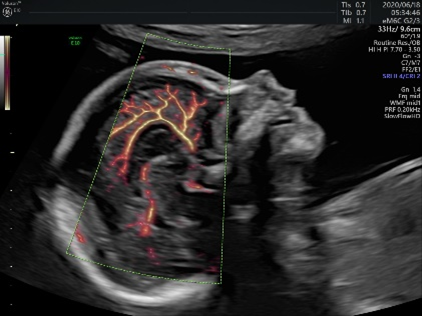

妊娠初期超音波検査は妊娠11週~13週の時期に行う、FMFのプロトコールに沿って詳細に行う超音波検査です。

まず、胎児の頭からお尻までの長さ(CRL)を計測して週数相当であることを確認すると同時に、解剖学的に大きな変化が胎児に認められ無いかどうかを診ていきます。

妊娠初期超音波検査を行う時期のCRLは45mmから84mm程度ですが、超音波機器の発達により詳細な解剖学的な所見を得ることが可能です。

最近の超音波機器の性能はとても高くなってきており、小さな胎児でも超音波検査で、「大きな心臓の変化」「初期の中枢神経の変化」など、構造学的な異常が検出されるようになってきました。